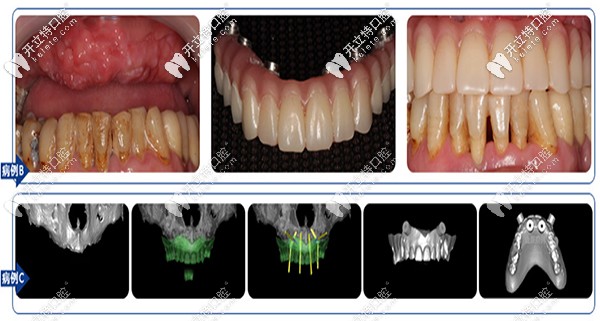

【沈陽盛大口腔全口、半口缺失案例】

沈陽盛大口腔全口、半口缺失案例

【沈陽盛大口腔多顆牙缺失】

沈陽盛大口腔多顆牙缺失

盛大口腔在種植牙方面,No belClinician軟件直觀模擬治療方案、種植導(dǎo)板定制,2小時戴牙,即可解決牙齒缺失。